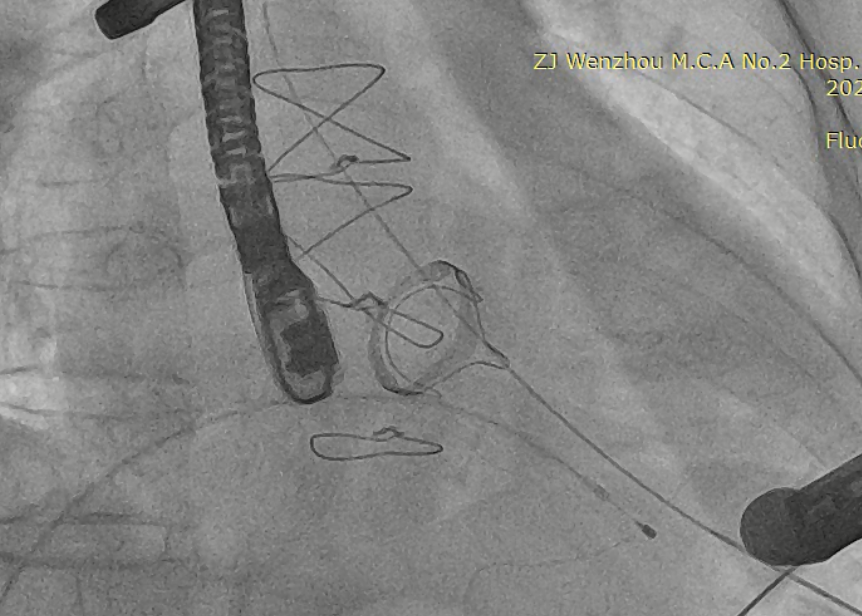

猪尾导管过瓣环平面进左心房

交换加硬导丝

扩张鞘预扩心尖穿刺点

输送器进入左室至生物瓣下方

左房内未见对比剂显影